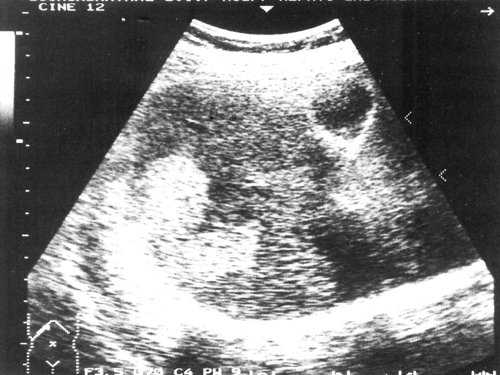

Женщина 50 лет, госпитализирована с болями в верхнем правом квадранте живота. Ультразвуковое исследование органов брюшной полости было проведено в день поступления (рис. 1а, б).

Рис. 1. УЗИ печени.

a) На эхограмме в правой доле печени видны два гиперэхогенных образования с четкими контурами (3,0x1,5 см, 2,5x1,5 см).

б) На эхограмме в левой доле печени видно большое гетерогенное образование (5.0x4.0 см), имеющее дольчатое строение.

Диагноз - множественная гемангиома печени